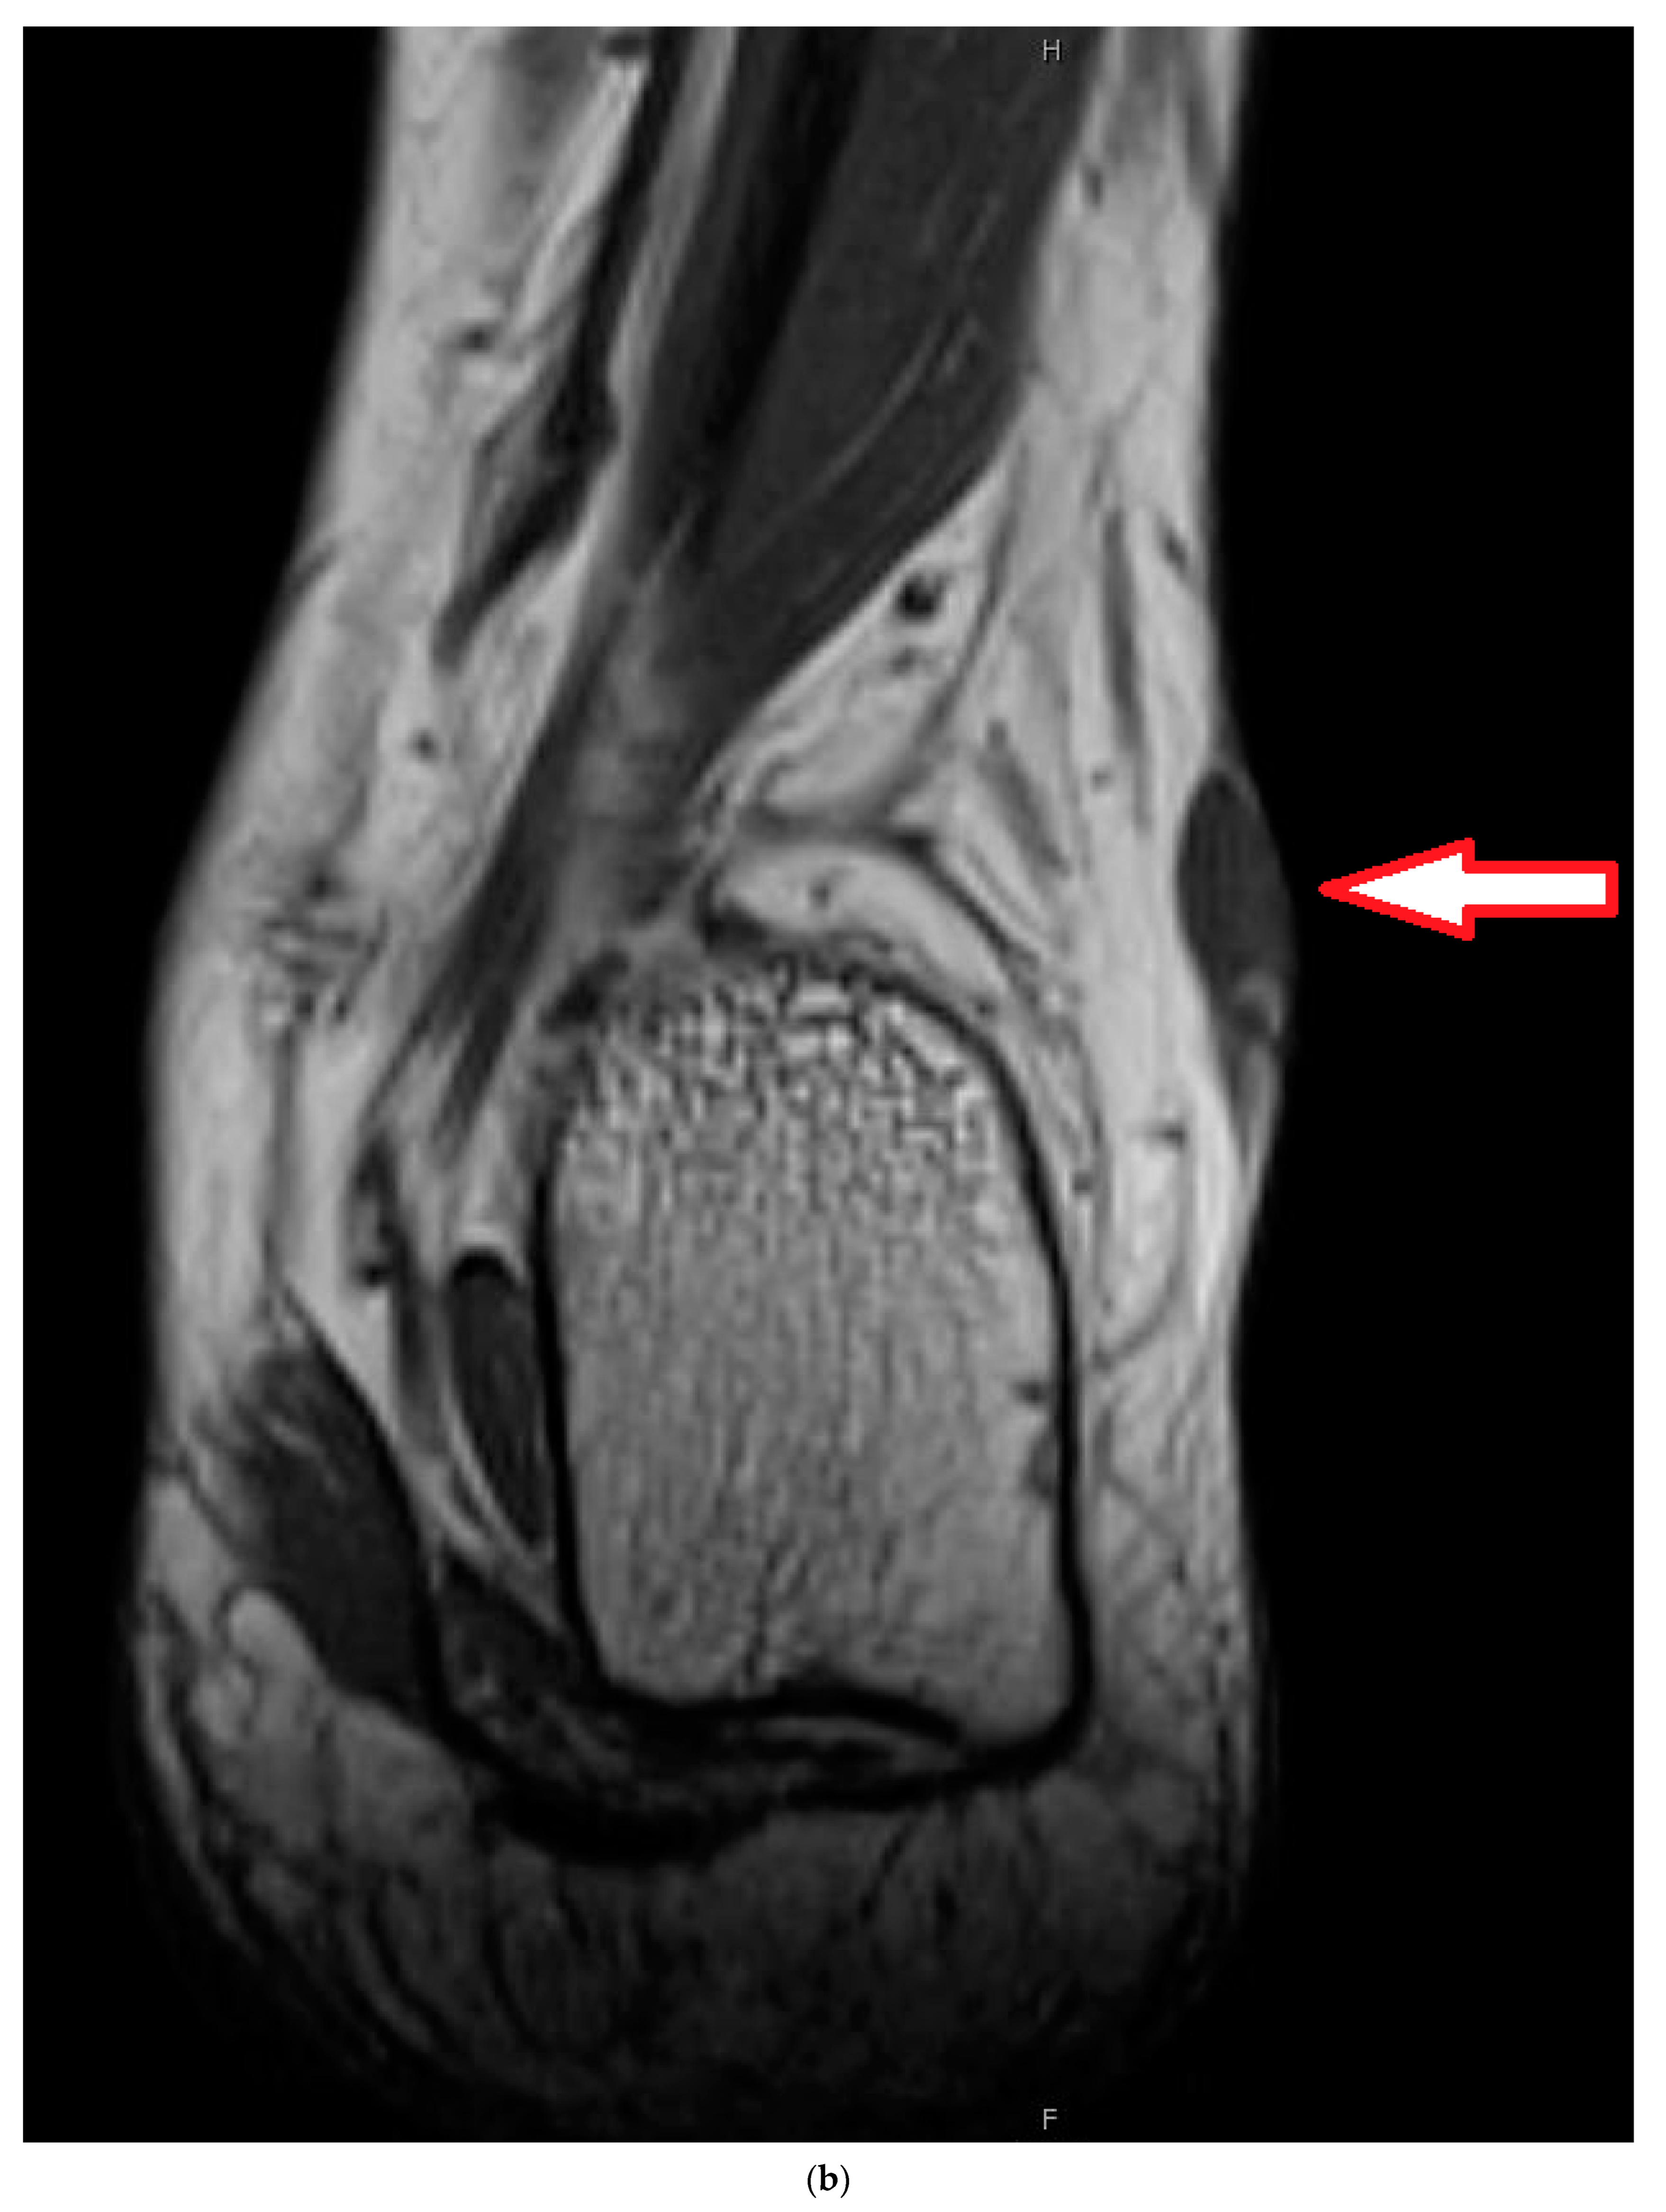

4. Illustrating Case